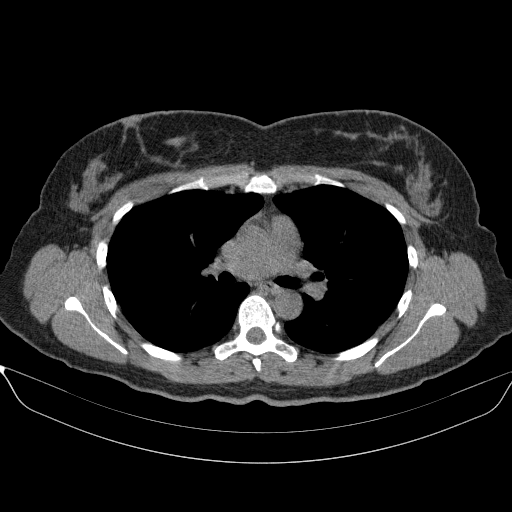

Slice 70 Targeting Evaluation

Slice: Slice_70

Slice Thickness: 1.5mm

Conversion: NATIVE β†’ VENOUS

Targeted Slice 70 - Mediastinum Window Analysis (Generated vs Real Venous)

0.741

Mediastinum SSIM

34.8

Mediastinum RMSE

13.6

Mediastinum MAE

Average Mediastinum Window Metrics Across All Slices (170 slices) - Generated vs Real Venous

0.728

Mediastinum SSIM (Avg)

35.8

Mediastinum RMSE (Avg)

14.6

Mediastinum MAE (Avg)

Original VENOUS CT scan

No window - Raw intensity values

Mediastinum window (WL 40, WW 400 β†’ Low βˆ’160, High +240)